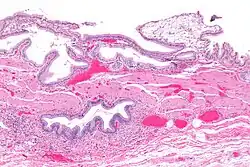

Eine chronische Cholezystitis kann zu einer Verhärtung der Wand mit Verkalkungen führen (Porzellangallenblase).